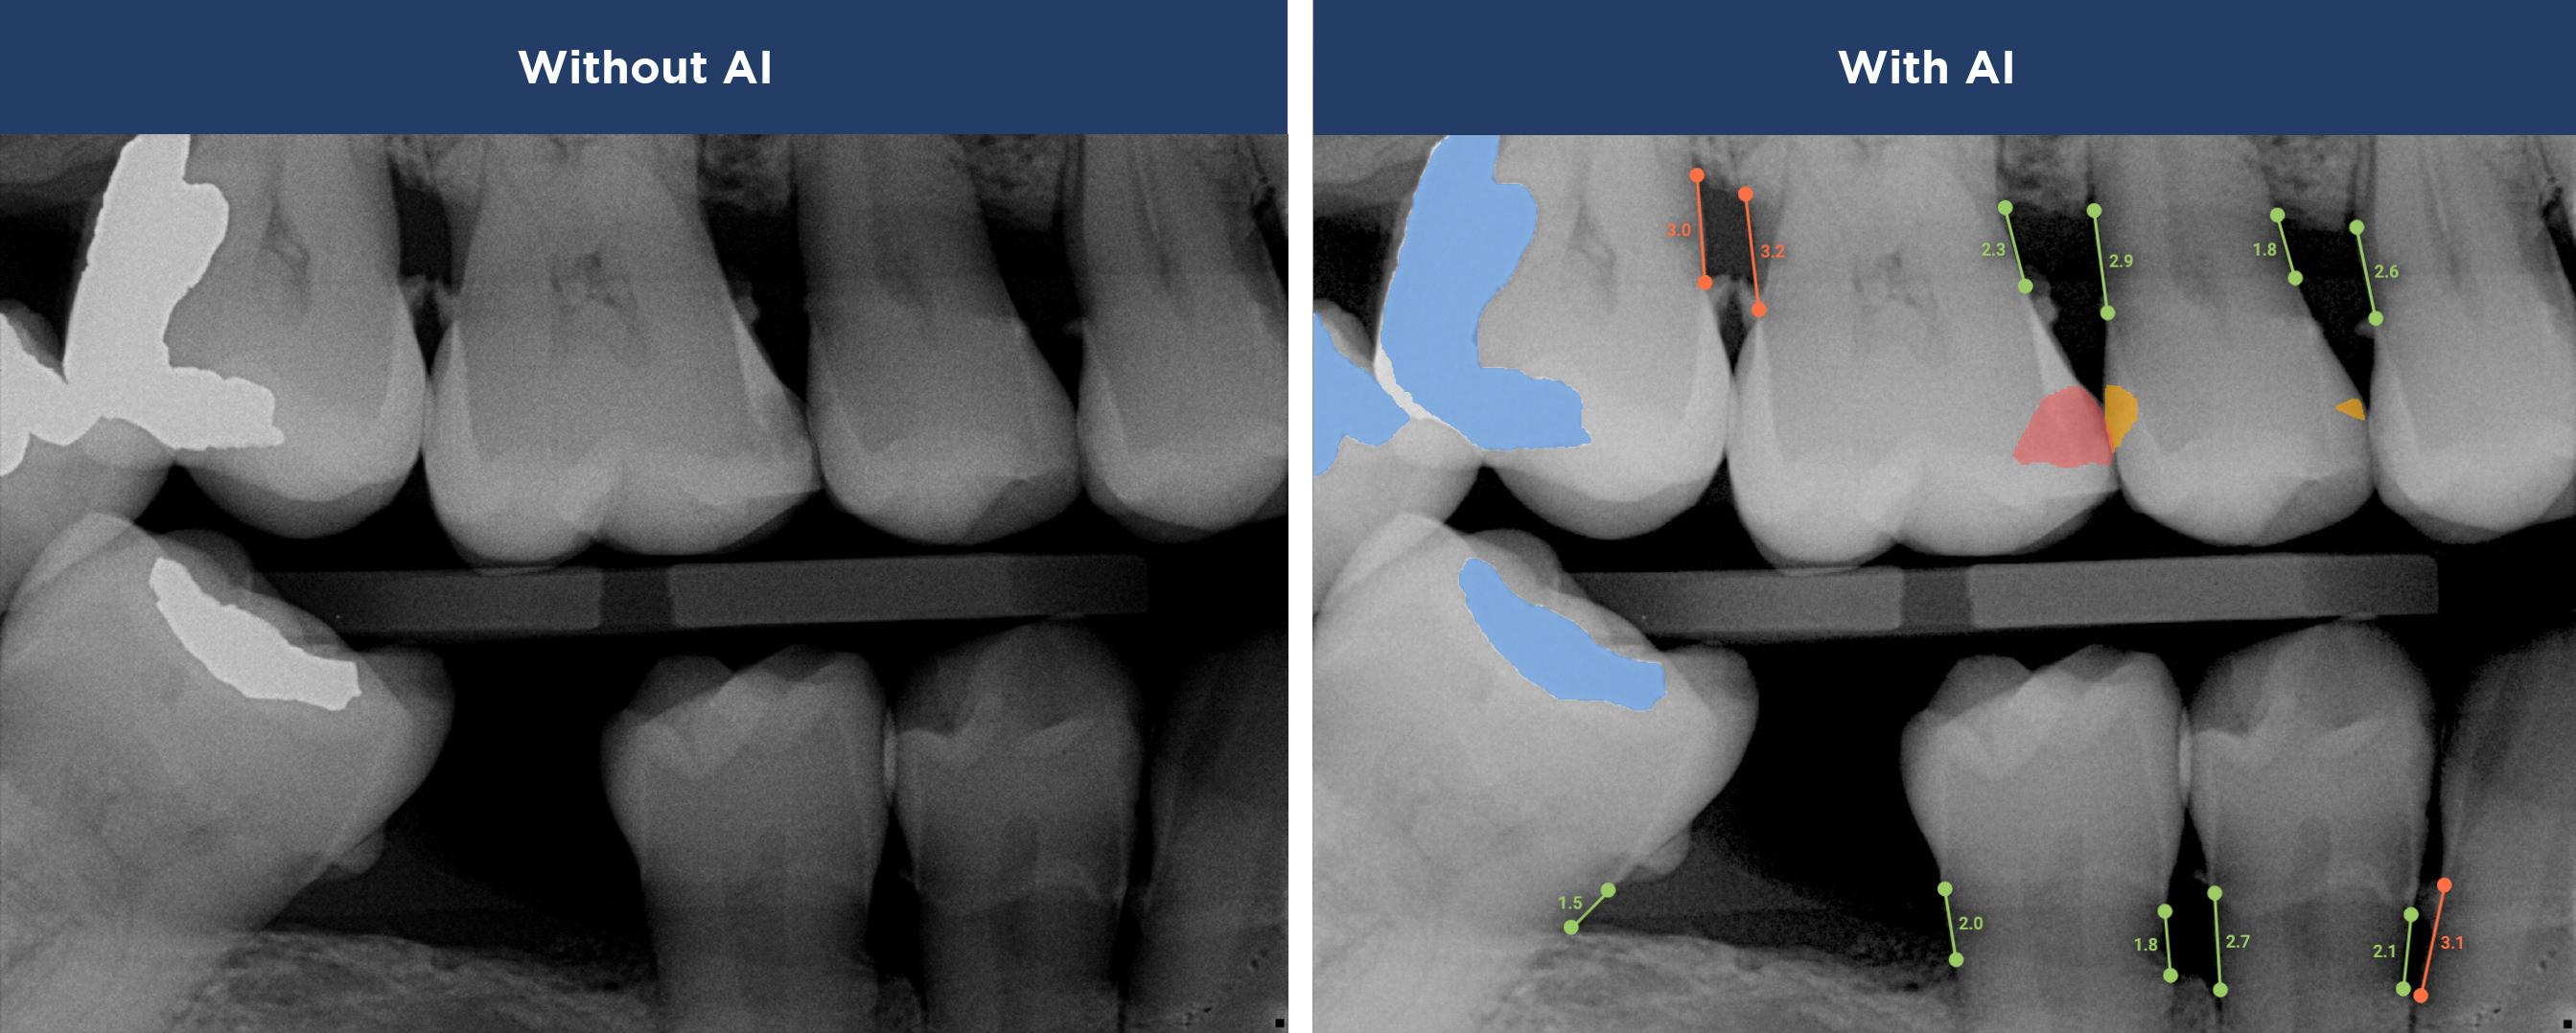

See More with AI

Where Advanced Technology Meets Personalized Care

Overjet AI's  patient-centric technology combines human intelligence with the power of artificial intelligence.

Best in class dental care for every patient, on every visit.

Confidence in Your Diagnosis

Our practice is proud to provide the best technology in the dental industry, including Overjet AI for instant X-ray analysis.

Overjet’s artificial intelligence technology transforms traditional black-and-white X-rays by adding a layer of data that instantly outlines decay (cavities) and measures bone loss. This makes it easy for you to see your results alongside your dentist.  It’s like getting a second opinion delivered instantly. With Overjet’s analysis and easy-to-read presentation, you will have the information you need to make an informed decision about your oral health. Together, we’ll review your findings and discuss the best steps to take to achieve your goals.